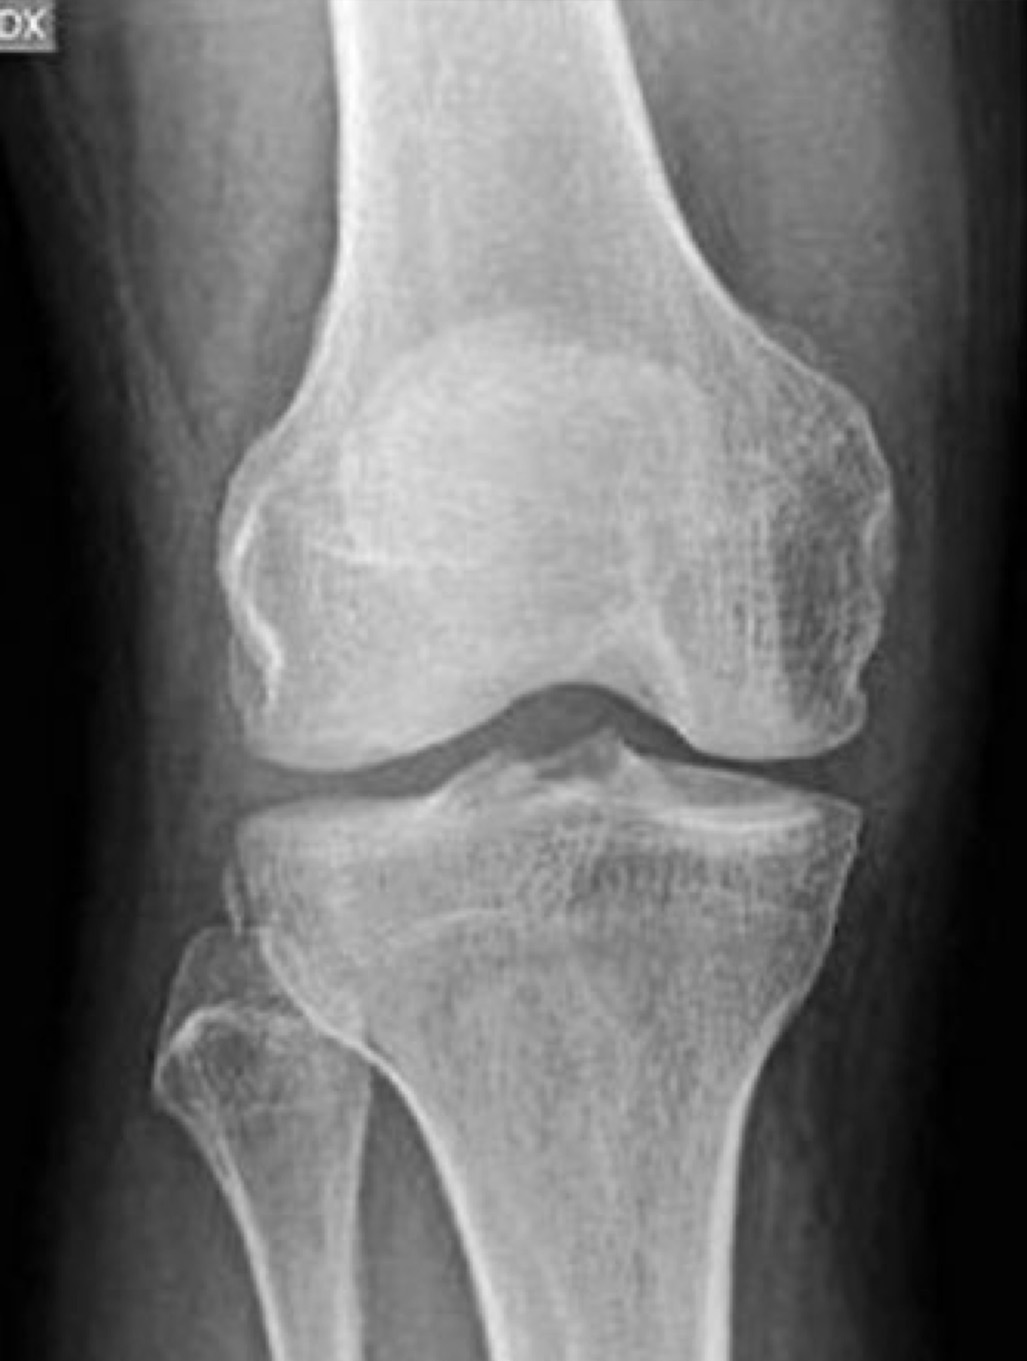

Na sequência de um evento agudo, deverá ser realizada uma avaliação por Raio X. Existe um sinal indireto de lesão do LCA, Sinal de Segond em até 75% dos casos, representando um arrancamento capsular lateral/avulsão da inserção do ligamento antero-lateral – Figura 5.

Sinal de Segond

Figura 5 – Sinal de Segond